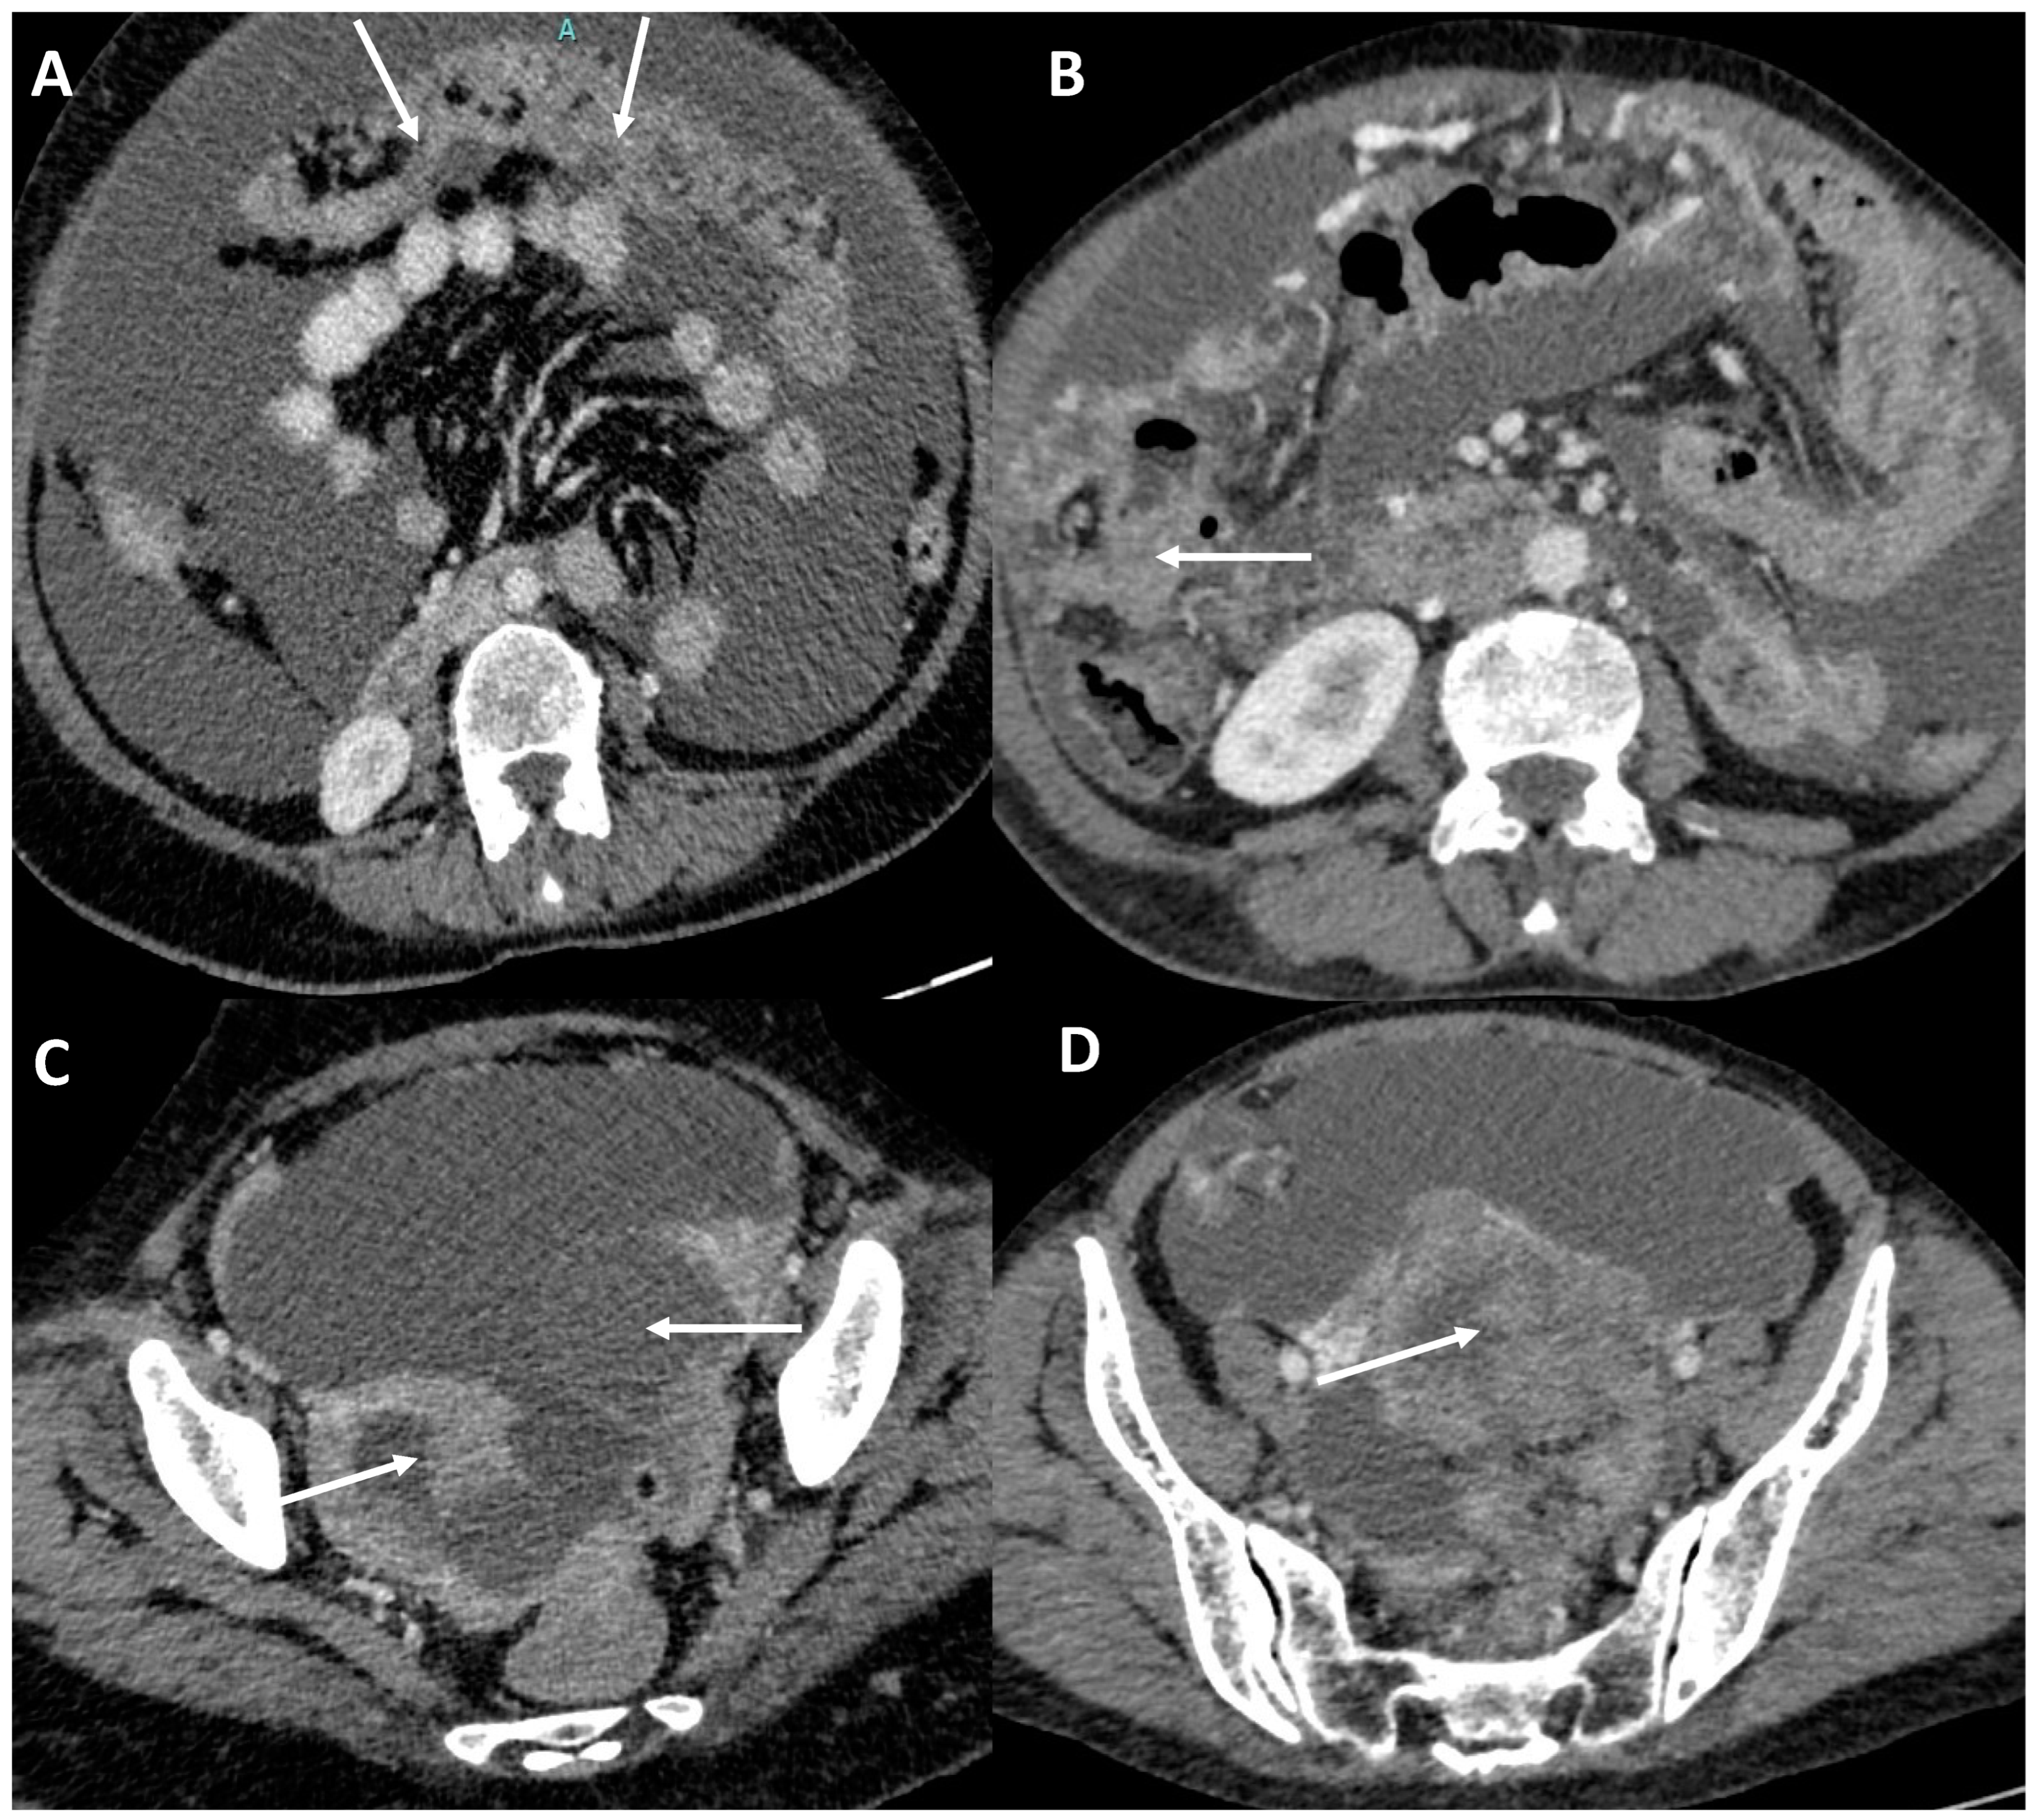

3.4. Peritoneal Involvement

3.5. Predictors of Peritoneal Carcinomatosis